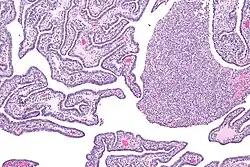

| Micrograph of acute and chronic salpingitis. H&E stain. | |

Salpingitis can be acute, chronic, or subclinical.[4]